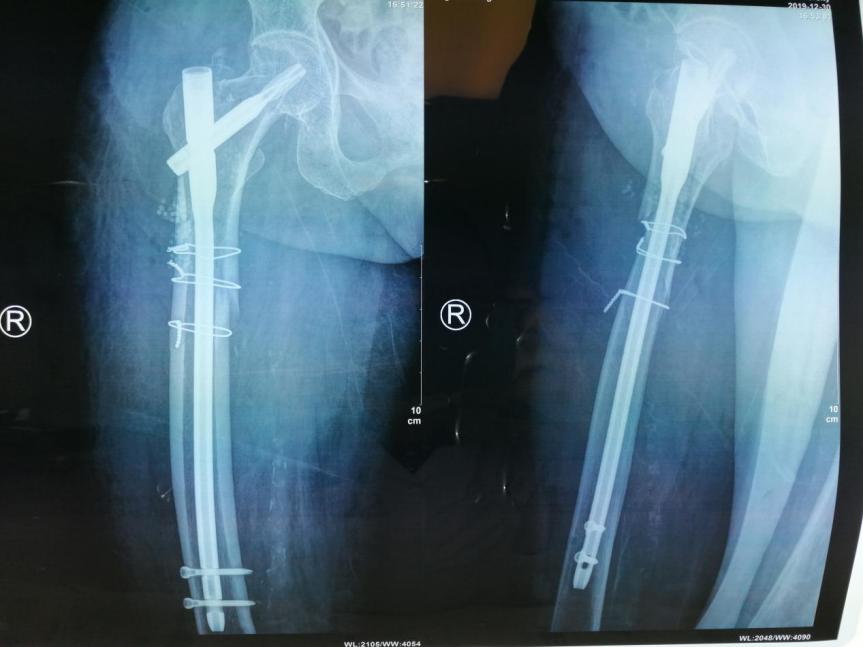

手术情况:2019年12月30日送手术室在麻醉下行右股骨上段粉碎性骨折切开复位防旋股骨近端髓内钉(proximal femoral nail antirotation,PFNA)内固定术。

术后影像学

术后片

右髋CT平扫:右股骨上段骨折内固定术后复查:右股骨粗隆间骨折线尚清,邻近见多发分离小碎骨影,右股骨近端见内固定影物,未见明显断裂征象,内固定周围股骨上段骨质断裂,骨折线尚清晰,可见部分骨痂生长,断端对位对线可。